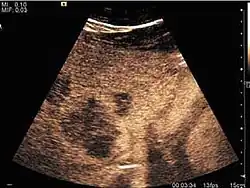

The ultrasound appearance is a well defined lesion, with very thin, almost unapparent walls, without circulatory signal at Doppler or CEUS investigation. The content is transonic suggesting fluid composition. The presence of membranes, abundant sediment or cysts inside is suggestive for parasitic, hydatid nature. Posterior from the lesion the acoustic enhancement phenomenon is seen, which strengthens the suspicion of fluid mass. They typically displace normal liver vessels but no vascular or biliary invasion occurs.

-

Liver cyst -